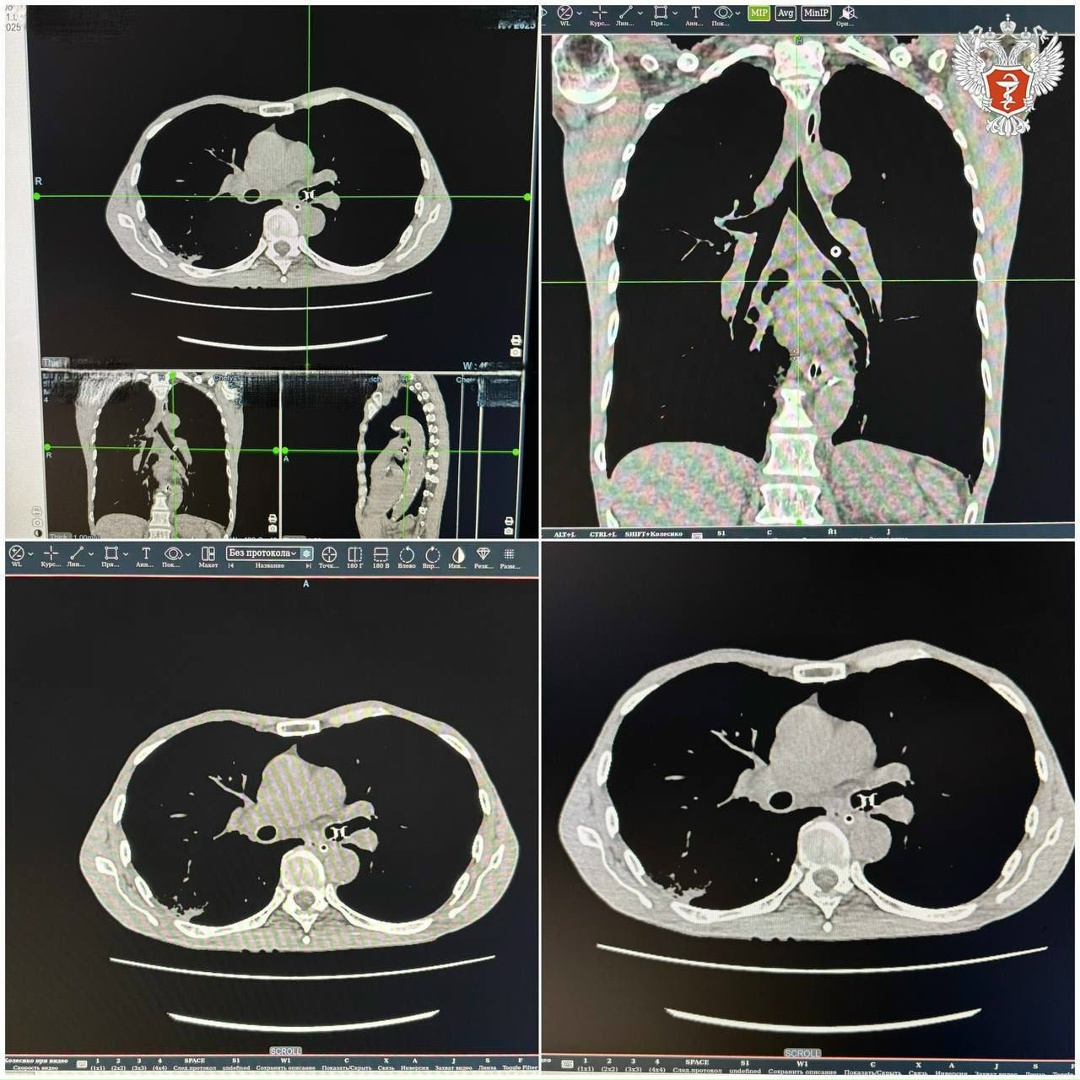

➡️ В ходе компьютерной томографии врачи выявили инородное тело в левом бронхе. Ранее пациенту установили голосовой протез после операции на трахее, а спустя время вспомогательный девайс «провалился» в бронхи.

— Левое легкое у него было полностью перекрыто, дышал правым легким. Такое попадание грозит местным воспалением, кровохарканьем, перфорацией органа и даже остановкой дыхания. Извлечь такие предметы тоже бывает непросто. Нам повезло, что предмет застрял в левом главном бронхе, там, где широко и удобная форма для захвата, — рассказала эндоскопист Челябинской городской клинической больницы №1 Юлия Клепинина.